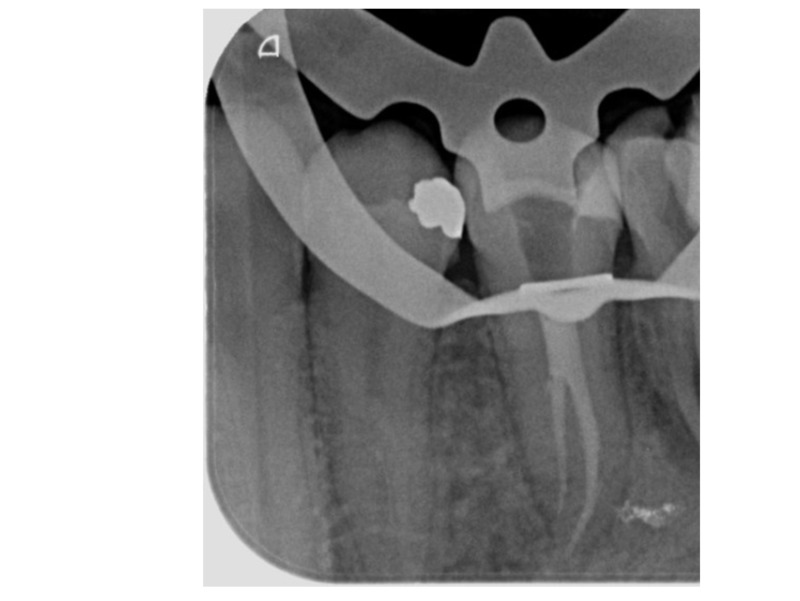

• Čtení RTG snímků, CT vyšetření

• Hledání vstupů a sondáž kořenových kanálků

• Výrazně zahnuté kořenové kanálky